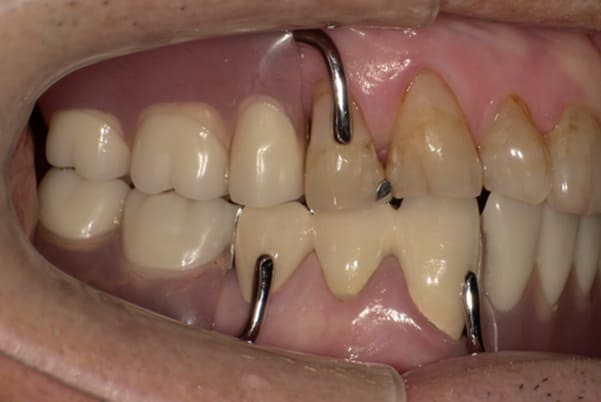

残りの歯に負担がかからないよう、被せ物と入れ歯の一体化を図った入れ歯

治療前は上下奥歯の入れ歯が削れていることで、かみ合わせが低くなり唇もつむった状態でした。

かみ合わせを適切な高さに戻したことで、本来の自然な口元へ。